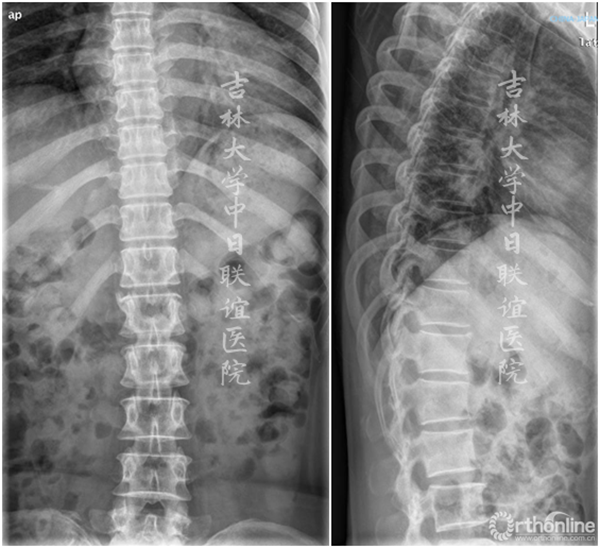

胸腰段X线/CT:未见明显异常

1.术前定位。术前常规完善正侧位X线片检查。开刀之前必须确定手术节段,通常采用20ml注射器无菌针头置于病变节段椎体棘突上进行C型臂下透视,并与术前正侧位X线片对照进行定位。

(1)对于下腰椎以骶骨为标志进行定位;

(2)对于胸腰段或下胸椎通常需要2枚针头,自骶骨向近端依次定位;

(3)对于上胸椎的定位通常采用正位胸1为标志向远端依次定位;

(4)对于颈椎通常以颈2为标志进行定位;

(5)其他常用的有助于定位的标志有:孤立的较大的椎体前缘骨赘、侧位像上第12肋骨、相邻的楔形椎等。